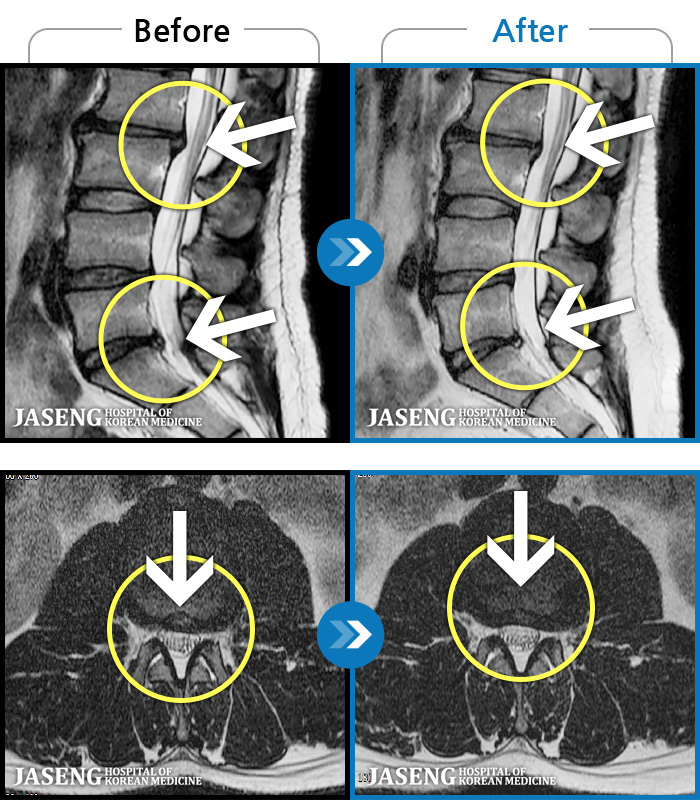

1,237 MRI ũ ʸ Ȯϼ.

㸮 ϻ .